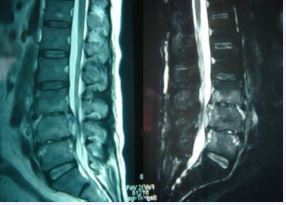

MRI showed that 70 patients with diseased vertebral bodies and intervertebral discs showed heterogeneous signals, in 18 cases, paraspinal features were thin and irregularly enhanced abscess walls and abnormal signals in poorly defined soft tissues, T1WI showed low signal, and T2WI showed high signal; Eleven patients had poor lumbar spine stability and spondylolisthesis; 42 patients showed uneven hypersignal in the vertebral body, intervertebral disc, and spinal canal on T1WI, T2WI, and fat pressure images, and the corresponding plane dura or nerve root compression (Figure 6).

Figure 6 L3-5 Brucellosis spondylitis. MRI showed thin irregularly enhanced abscess wall and soft tissue abnormal signal with ill-defined borders around the spine, low signal on T1W, high signal on T2W, and heterogeneous high signal in vertebral body, intervertebral disc, appendix and spinal canal on fat-pressed images , the corresponding spinal cord plane is compreressed.

The advantages of CT-guided puncture abscess and biopsy are also available. In this group, 53 cases had the characteristic manifestation of “lace vertebrae” and 17 cases formed “lipshaped” osteophytes, and 18 cases showed paravertebral abscesses; The main value of MRI examination is to display abnormal signals at the stage of inflammatory infiltration, to determine the involvement of the spine and the scope of lesions, and to clearly show vertebral osteomyelitis, intervertebral disc destruction, paravertebral abscess, and intraspinal epidural abscess. Damaged intervertebral disc or inflammatory granulation tissue protrudes into the vertebral canal, causing compression of the corresponding plane dural sac [2,7,8]. MRI can guide surgical treatment, 44 cases of this group MRI showed dural sac or nerve root compression. Pathological manifestations include histiocytosis and non-tuberculous granuloma formation. Microscopically, infiltration of neutrophils, monocytes, lymphocytes, and eosinophils was observed, and proliferative nodules composed of patches of epithelioid cells were visible. In this group of 42 patients, pathological examination was performed on all lesions removed during surgical treatment, which conformed to the histological findings of brucellosis [1,7].